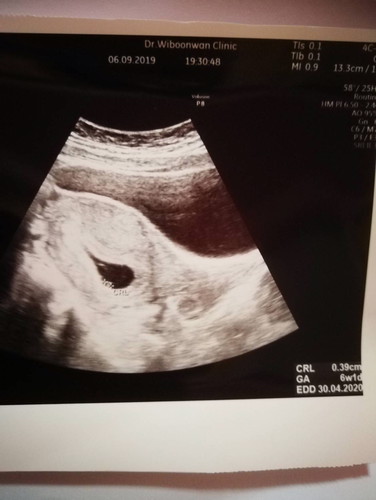

คือเราได้ไปฝากท้องกับทางโรงพยาบาลใกล้บ้านแล้ว อายุครรภ์ ถ้านับตามวันที่ประจำเดือนมาครั้งสุดท้าย ตอนนี้ได้9w พอเมื่อวานเราอยากจะไปอัลตราซาวด์ที่คลินิค อยากรู้ว่าลูกจะมีหัวใจรึยัง ปรากฏว่า คุณหมอบอก เห็นแต่ถุงตั้งครรภ์และถุงไข่แดง แล้วอายุครรภ์ในเครื่องอัลตราซาวด์คือ6wเอง ยังไม่เห็นเด็กและก็หัวใจเลย คุณหมอนัดอีกที1อาทิตย์ให้กลับมาซาวด์ใหม่. เรานี่เครียดเลย กลัว จิตตก กังวลไปหมด มีแม่ๆคนไหนซาวด์ตอนอายุครรภ์เท่านี้แล้วเจอแบบเราบ้างคะ??